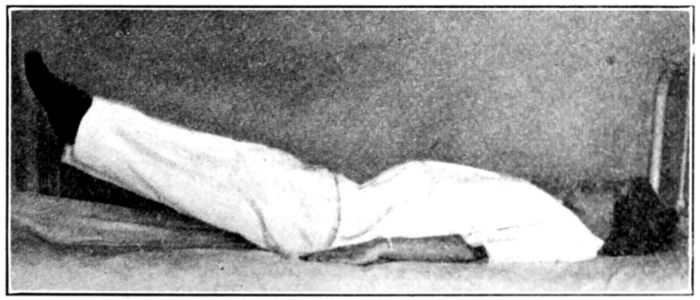

| 129, 130, 131, 132, 133, 134, 135. | Bed exercises taken during the puerperium | 350 to 353 |